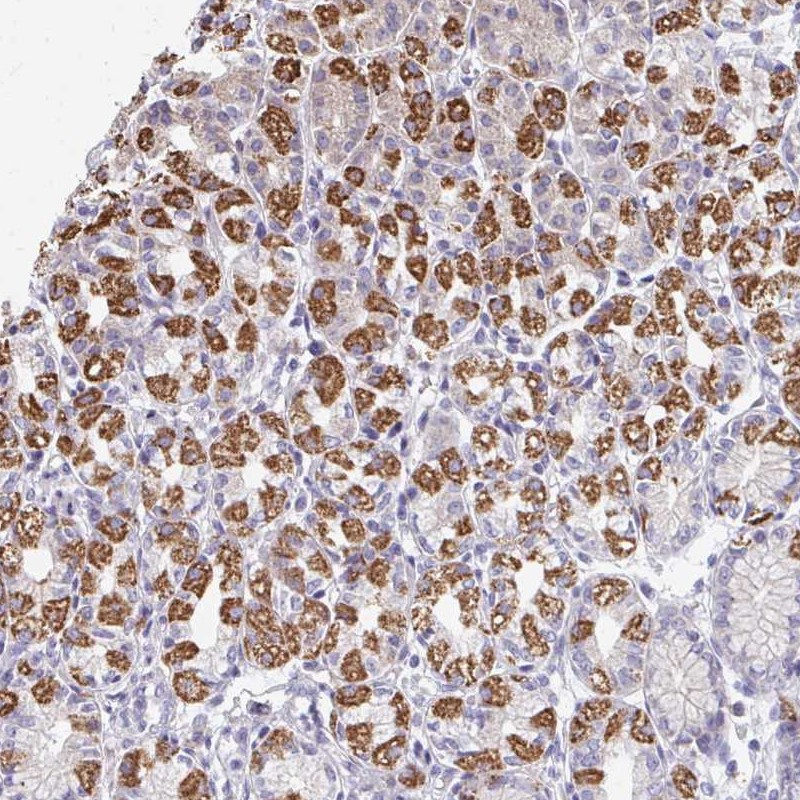

Immunohistochemical staining of human stomach, upper shows strong cytoplasmic positivity in glandular cells.